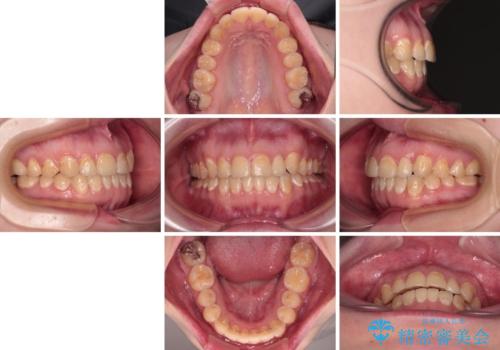

舌側転位している側切歯特有の、切縁の位置が不揃いであったり、根元が内側に引っ込んだ状態であったりという、インビザライン独特の仕上がりになることなく、きれいに整った歯列とすることができました。

- 前歯のデコボコとクロスバイトが気になり、インビザラインによる矯正治療を希望して来院された患者様です。

上顎側切歯(上の真ん中から2番目の歯)が舌側転位している場合、無理して動かそうとすると歯髄壊死を起こすリスクが高い印象があります。

インビザライン単体でも治療は可能ですが、安全策としてインビザラインで歯列を移動する前に上顎前歯をワイヤー矯正で整え、その後上下歯列をインビザラインにて矯正治療を行うこととしました。